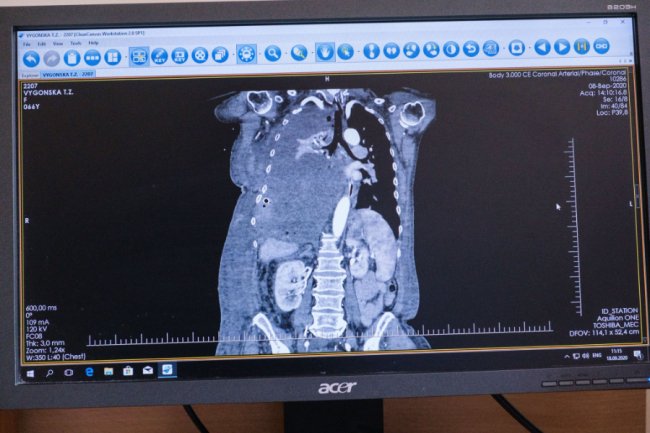

У травні Тетяна Вигонська відчула сильну задишку та слабкість, тому була змушена звернутися по медичну допомогу. У Хмельницькій обласній лікарні їй поставили діагноз – солітарна фіброзна пухлина правого гемітораксу.

Новоутворення затиснуло праву легеню й давило на ліву легеню та серце. Через розмір пухлини жінку відмовились оперувати у Хмельницькому.